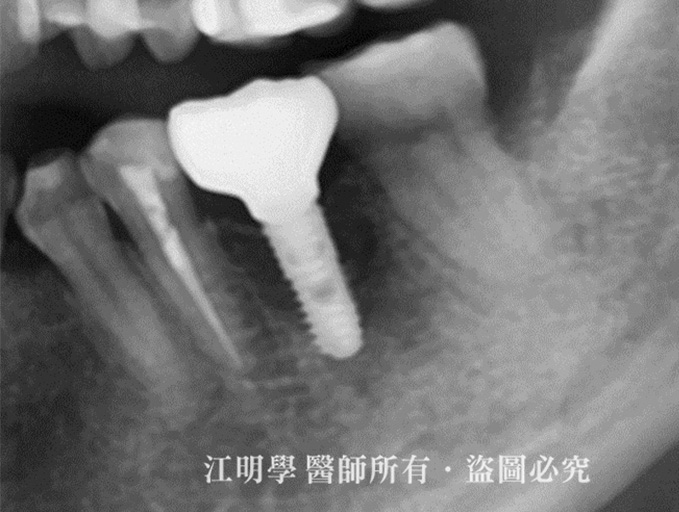

治療前:缺牙部分做植牙手術,並做咬合的修正

治療後X光